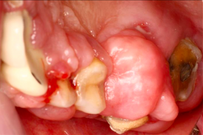

Case Background

A 65-year-old female on antihypertensives and immunosuppressants presented with severe gum swelling, inability to chew, and difficulty maintaining oral hygiene. This led to multiple decayed and periodontally compromised teeth, worsening her overall condition.

Before Treatment